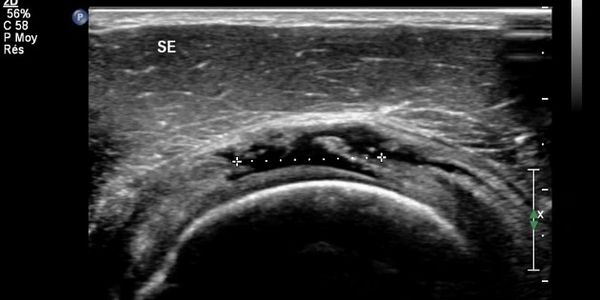

Musculoskeletal ultrasound is a safe and effective modality that allows your physical therapist to see the muscle, tendon, or joint where you feel pain. During your session your doctor of physical therapy may choose to utilize this imaging technique to aide in your diagnosis, or to ensure that your tissues are responding appropriately to therapy.

Diagnostic Ultrasound offers a number of important advantages compares to X-Ray, CT, and MRI in terms of safety and effectiveness. Diagnostic ultrasound in noninvasive and offers real-time imaging, allowing for examinations of structures at rest and in motion. This ability to capture the movement of the musculoskeletal components differentiates it from other imaging modalities and can permit a more accurate diagnosis.

Additionally, MSKUS uses high-frequency wounds waves that are transmitted from the probe through gel and into the body. The transducer collects the sound waves that bound back and the use those sound waves to produce an image. Ultrasound examinations does not use ionizing radiation (as used in X-Rays and CT Scans), thus there is no exposure to the patient or therapist. Because ultrasound images are captured in real-time, they can show the doctor how the body responds to mechanical stress, providing vital information to your examination and treatment protocol.